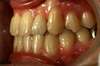

Intra Orale Droite

Intra Orale Gauche